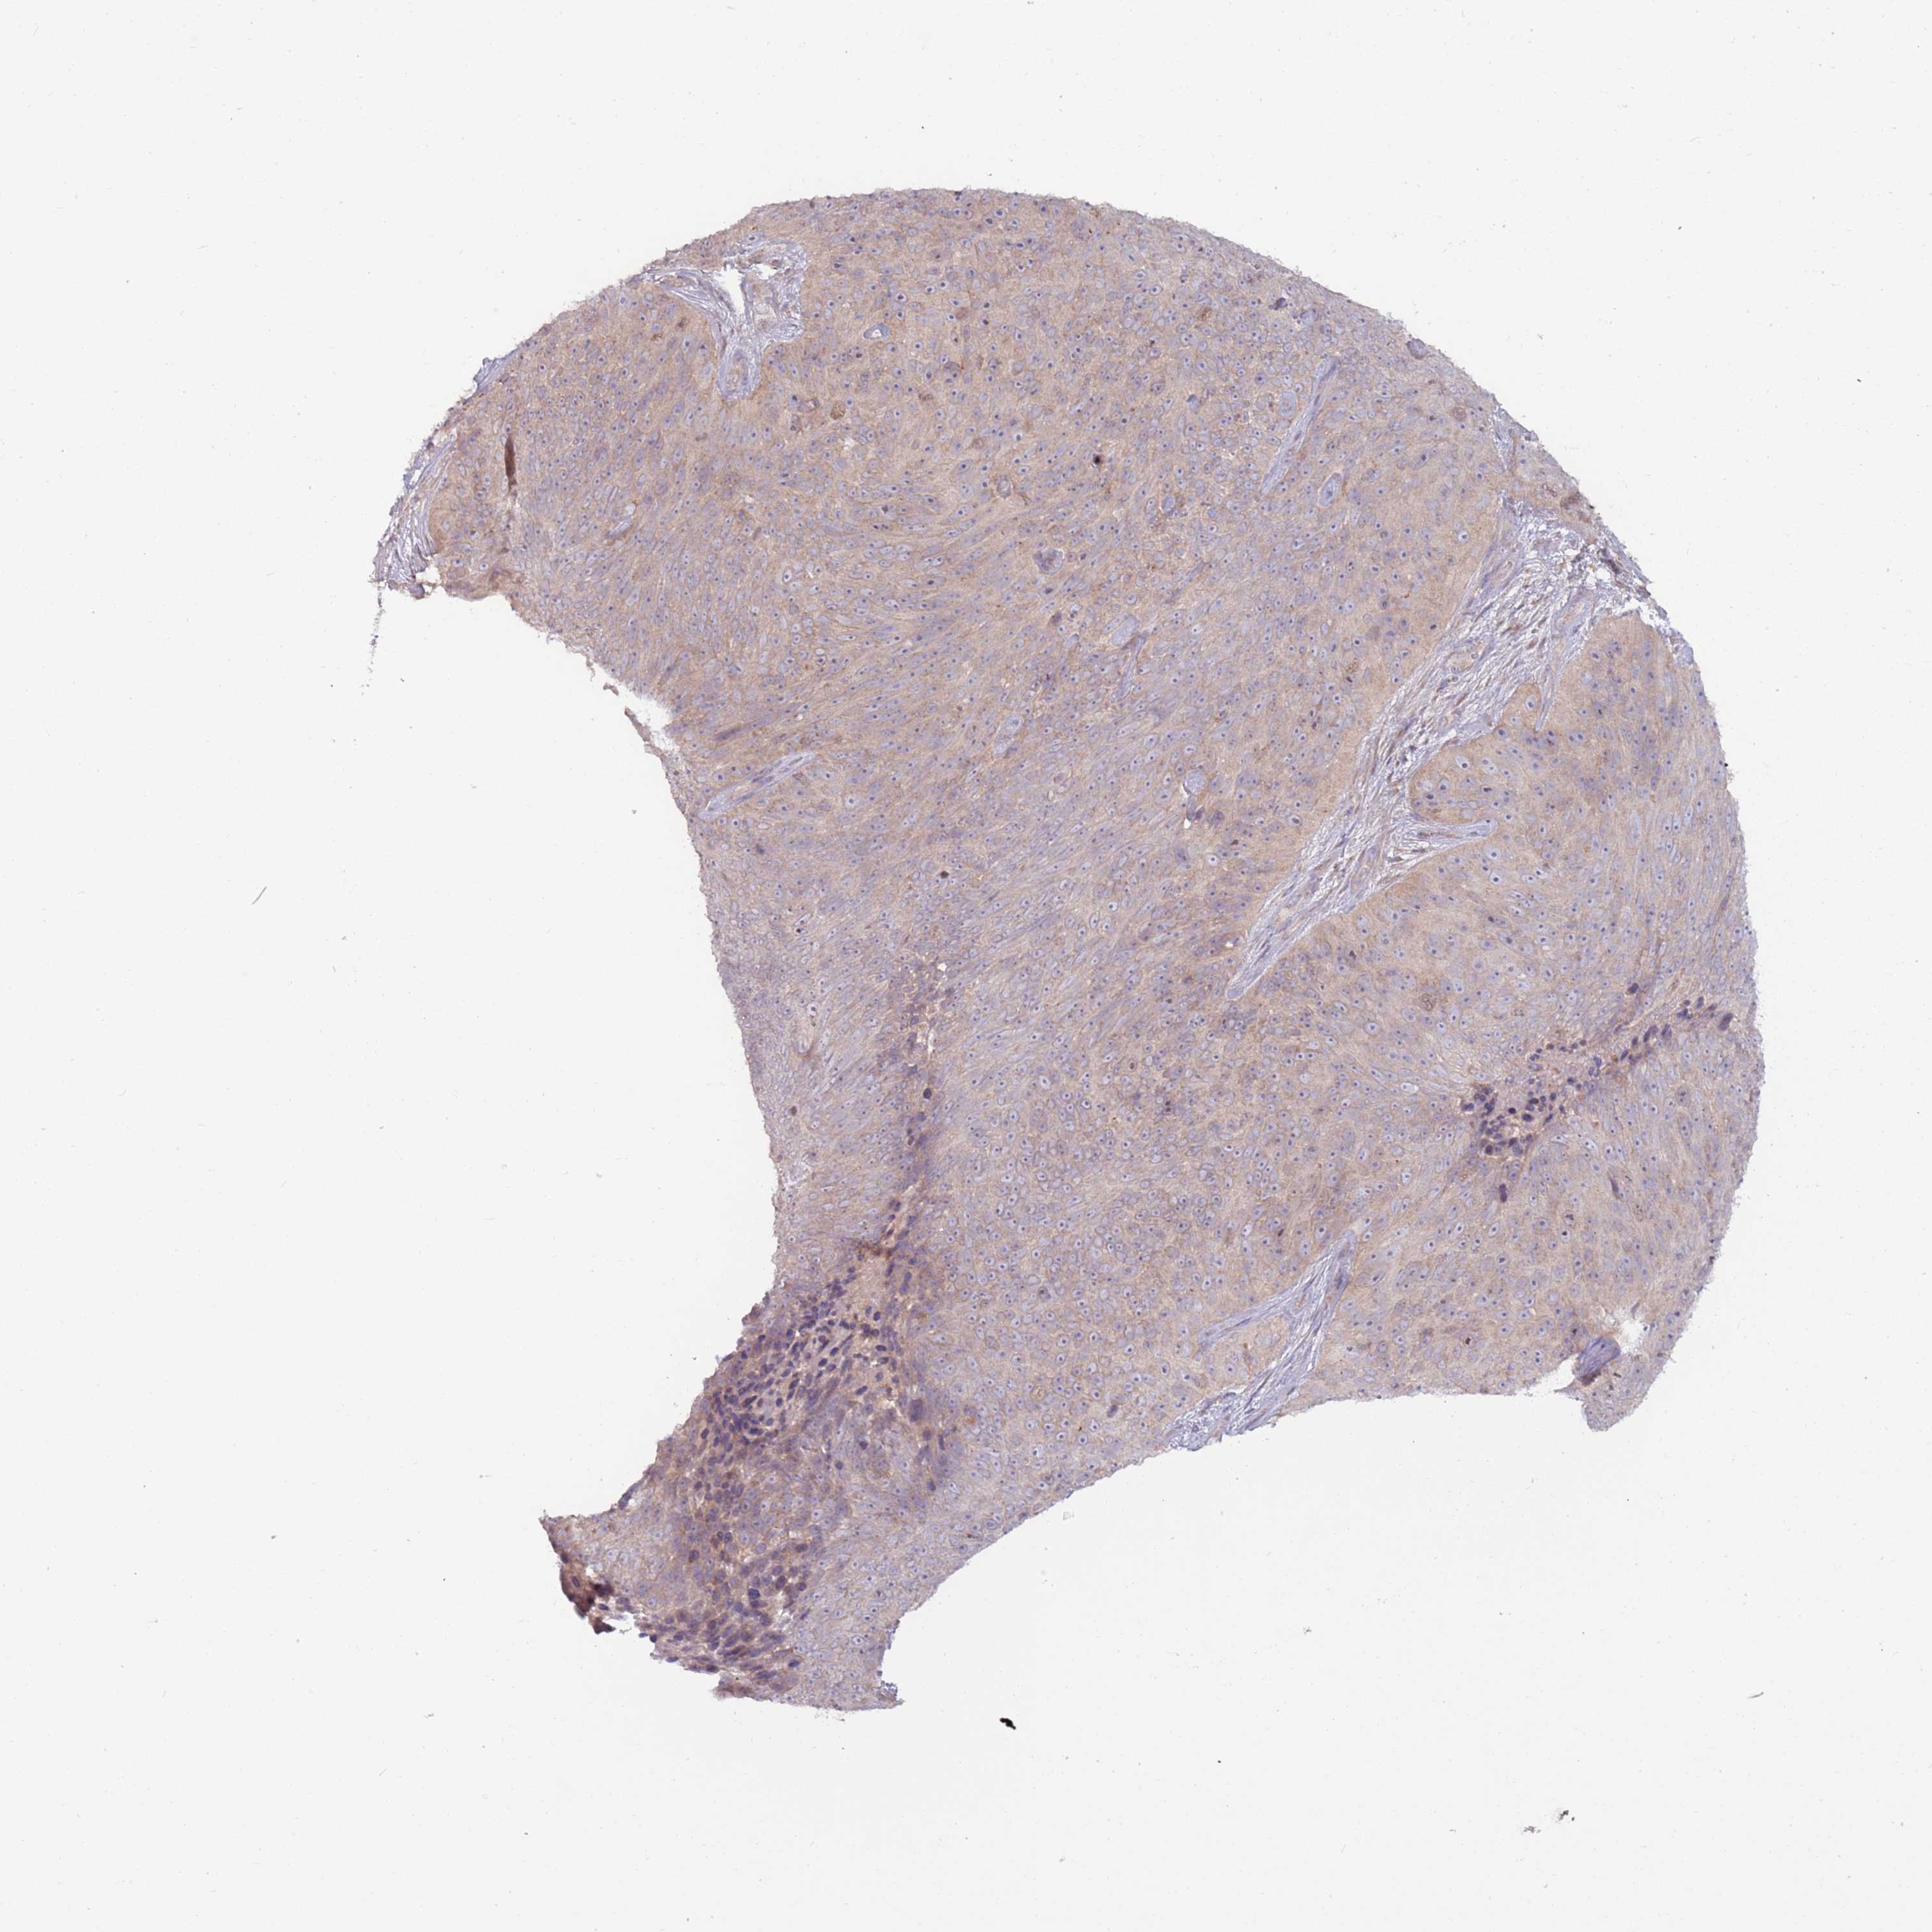

SKIN CANCER - Protein expressioni

A mouse-over function shows sample information and annotation data. Click on an image to view it in a full screen mode. Samples can be filtered based on level of antibody staining by selecting one or several of the following categories: high, medium, low and not detected. The assay and annotation is described here.

Antibody stainingi

Antibody staining in the annotated cell types in the current human tissue is reported as not detected, low, medium, or high, based on conventional immunohistochemistry profiling in selected tissues. This score is based on the combination of the staining intensity and fraction of stained cells.

Each image is clickable and will lead to virtual microscopy that enables deeper exploration of all samples and also displays staining intensity scores, fraction scores and subcellular localization as well as patient and tissue information for each sample.

Antibody HPA001117

Staining

High

Medium

Low

Not detected

Intensity

Strong

Moderate

Weak

Negative

Quantity

>75%

75%-25%

<25%

None

Location

Nuclear

Cytoplasmic/membranous

Cytoplasmic/membranous,nuclear

Squamous cell carcinoma, NOS

Squamous cell carcinoma, metastatic, NOS